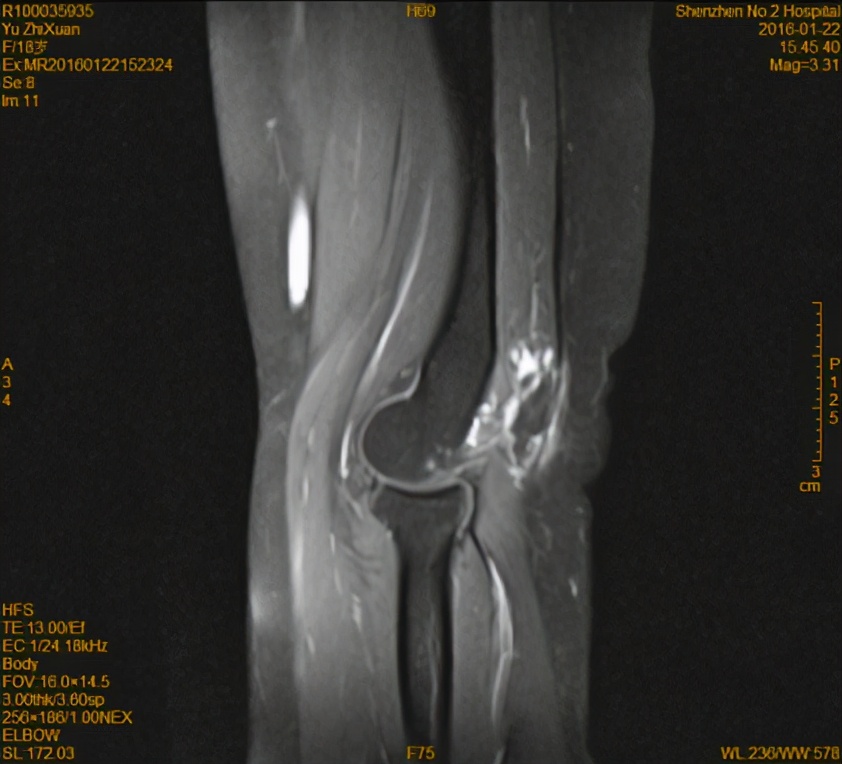

术后患者恢复良好,术后5个月复查,范围较前明显缩小,症状也明显缓解,患者非常满意。

(术后5个月MR T2WI)

(术后5个月MR 增强)